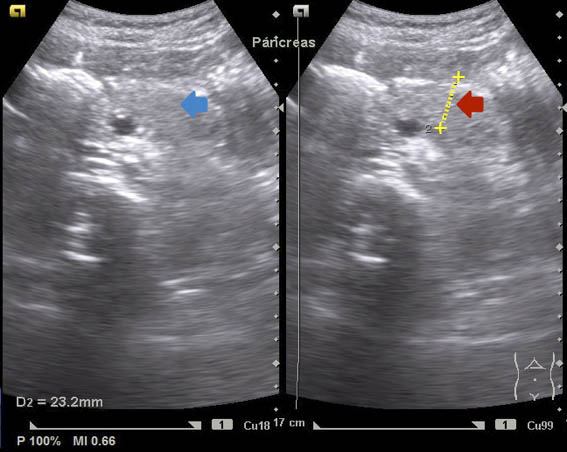

Fue hospitalizada en el servicio de Pediatría, donde se realizaron los siguientes estudios. Perfil inmunológico: factor reumatoide 2.67 UI/mL, velocidad de sedimentación globular 12 mm/h, anticuerpos anti-DNA doble cadena con resultado negativo, anticuerpos antinucleares negativos, complemento C3 93.6 mg/dL, complemento C4 29.9 mg/dL. Perfil infeccioso: anticuerpos IgG e IgM citomegalovirus negativos, anticuerpos IgG e IgM toxoplasma negativos. Radiografía de tórax simple: campos pleuropulmonares y ramas pulmonares normales, sin cardiomegalia o masas ocupativas (figura 1). Radiografía de abdomen simple: aire en cámara gástrica, de escasa cantidad en colon y recto; colon descendente y recto sigmoides con imágenes sugestivas de fecalitos (figura 2). Ultrasonido de hígado y vías biliares: páncreas en situación habitual, con bordes regulares bien delimitados, cabeza y cola dentro de los parámetros normales, cuerpo aumentado de tamaño, en forma de herradura, sin evidencia de líquido peripancreático; hígado y vesícula biliar conservados (figura 3).

La alimentación de la paciente, abundante en hidratos de carbono y grasas, y en alta cantidad, permitió sospechar una pancreatitis aguda y abordar el estudio desde la sala de urgencias como tal, encontrando en el ultrasonido15 datos de imagen compatibles con páncreas anular,16 dando lugar a su internamiento para completar su estudio.17